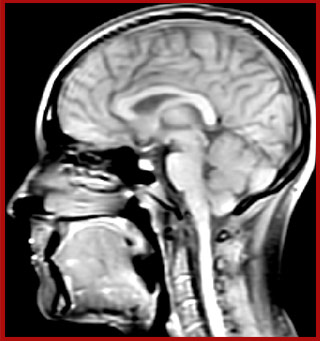

“In addition to traditional imaging like FLAIR for lesion identification, we see a real push towards techniques that weren’t normally required for MS, including good highresolution 3D T1 weighted images to do volumetrics. We’ve also started looking at spinal cord imaging again, since techniques have improved in terms of acquisition and analysis. Another important technique is susceptibility weighted imaging (SWI), particularly if we are looking for central veins in lesions, which is extremely helpful for diagnosis.”

The techniques for measuring myelin have changed a lot over the years. “Since we are using the Elition, our myelin water images are much better. We're now acquiring 1 x 2 x 5 mm voxels and displaying at 1 x 1 x 2.5 mm. For a whole brain we can now measure the fraction of water in the myelin component in only about five or six minutes,” Dr. MacKay says.

of limiting MWI to the brain, even without the cerebellum, we can now spend about the same amount of time and scan the whole brain and the cervical spinal cord, which is a huge boost for us.” Dr. Rauscher says, “For MWI we perform 3D T2 with 32 or more echoes. This used to take a long time, but with Compressed SENSE we can decrease this to ten minutes for the whole head. Because of the large field of view (FOV) on the readout direction, we even get information from the brainstem, which we previously missed when we were using the GRASE approach. Having the whole head scan is nice because it has spatial resolution, orientation and FOV that are comparable to the standard 3D clinical MS scans, including the FLAIR and 3D T2, and a 3D T1 for brain volume.”

According to Dr. MacKay, MWI images benefit from Elition’s high quality gradients. “We need good gradients because we want to be able to do multi-echo sequences that have short TE times.”